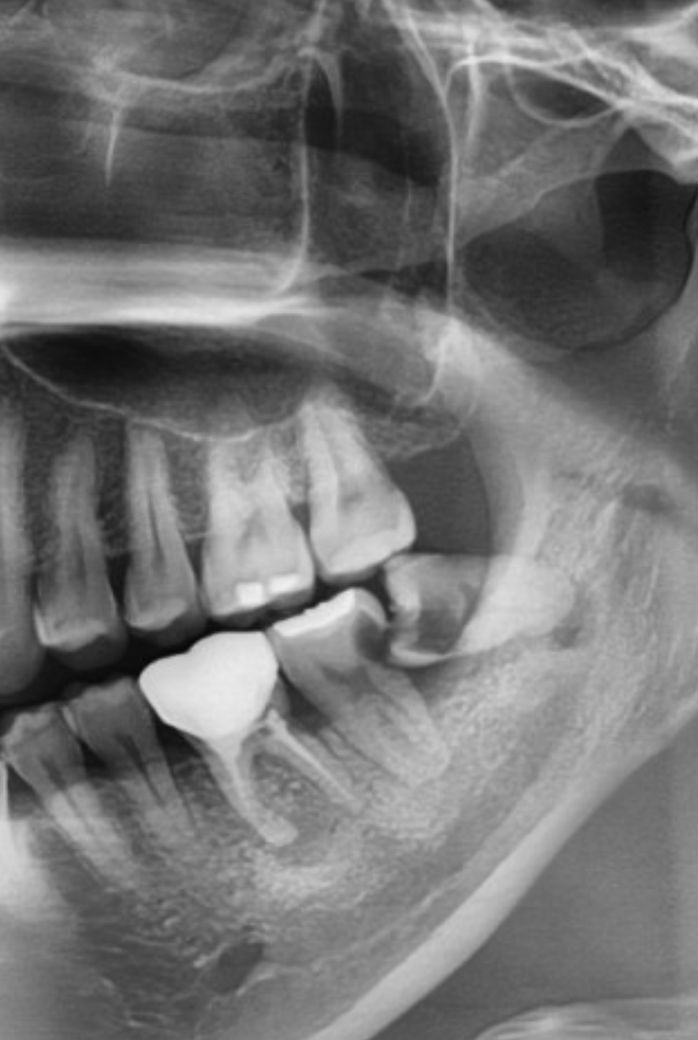

사랑니만 뽑을 순 없는걸까요..?

어금니 신경치료+크라운도 꼭 같이해야 하는건지..

기존에 치료했던 이라.. 혹시나 전문가 소견은 어떠신지 궁금해서 여쭤봅니다

엑스레이상 저정도로 보이는 충치면 사랑니 앞 어금니도 발치를 고려해야 할 정도로 큽니다.

일단은 사랑니 발치 후 신경치료하고 크라운으로 계획은 세우지만 신경치료자체도 쉽지 않은 치아이기에 아마 발치하고 임플란트 심자고 하는 치과가 대부분일 것 같습니다.

현재 상태에서는 충치가 매우 심해서 사랑니 발치 이후에 반드시 치료를 해야 합니다. 다만 치료 자체가 쉽지 않으며 현재 상태에서는 치아 발치도 고려해야 합니다. 상태를 보았을 때 충치가 뿌리 아래 부분까지 많이 내려가 있으며 이러한 경우에 치료 자체가 굉장히 어렵고 치료가 잘되더라도 얼마가지 못해 탈이나서 문제가 되는 경우가 많습니다. 현재로서는 치료하지 않을 수 없으며 발치까지 고려해서 치료를 진행해야 합니다.

빨리 사랑니 발치하시고 치료받으셔야합니다. 어금니도 방치시에는 발치해야하는 상황이며 지금도 우식 상당히 심한 상황입니다. 미루지마시고 빨리 진행하시기를 권유드립니다.